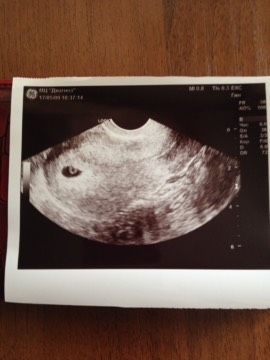

Вот моя кроха, пока эмбрион не визуализируется и сердечко рановато, сказали что через пару недель прийти..! Но главное нет ни угрозы, ни отслойки… плодное яйцо 8 мм, желточный мешок все на месте… Мы в домике, все на месте… Моя кнопка сильная..)) как же здорово осознавать что все у нас отлично..! Зря переживала вчера )) поставили 5 недель и три дня, вот мы красавцы… Первое наше фото))

У вас как будто колечко на фото))) поздравлю) легкой беременности вам)

Да я тоже вижу колечко)) спасибо вам большое??